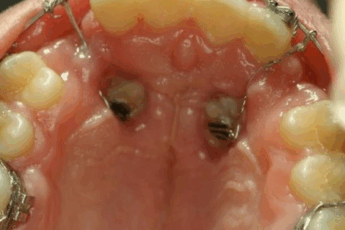

Mucocele: un bulto o quiste que se forma en la boca debido a la acumulación de saliva.

Absceso dental: una infección que causa dolor e inflamación alrededor de un diente.

Es importante destacar que algunas lesiones bucales pueden ser potencialmente malignas, como la leucoplasia y la eritroplasia, por lo que se recomienda buscar atención dental si se observan cambios en la boca.